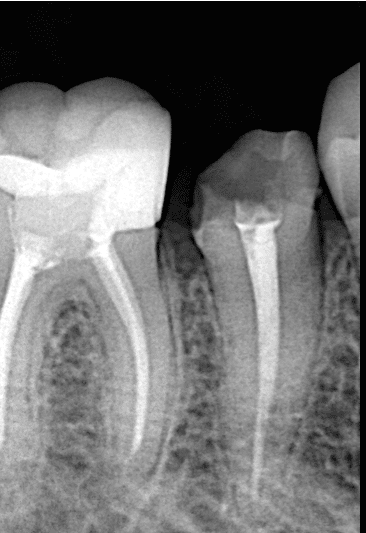

Pre-operative x ray

Treatment plan after x ray taking to evaluate the status of the root and bone and root canal treatment was to do DME and core buil up and supporting it with long and short fibers (ribbond and ever x flow ) to create strong biobase for the final indirect lithium disilicate overlay restoration